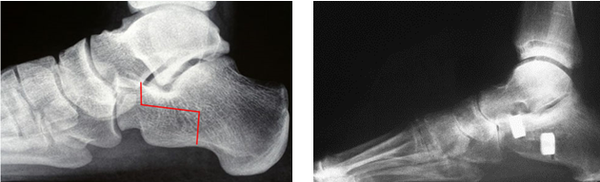

(Pre and post X-rays showing the line of the bone cuts and subsequently view post procedure with the calcaneum lengthened and rotated at the same time)

These X-rays show the foot from the side with initially a loss of arch height and a midfoot sag, in a young adult. Post procedure the lateral column has been lengthened using an Evans procedure with a navicular cuneiform fusion.

This has now been successfully realigned.